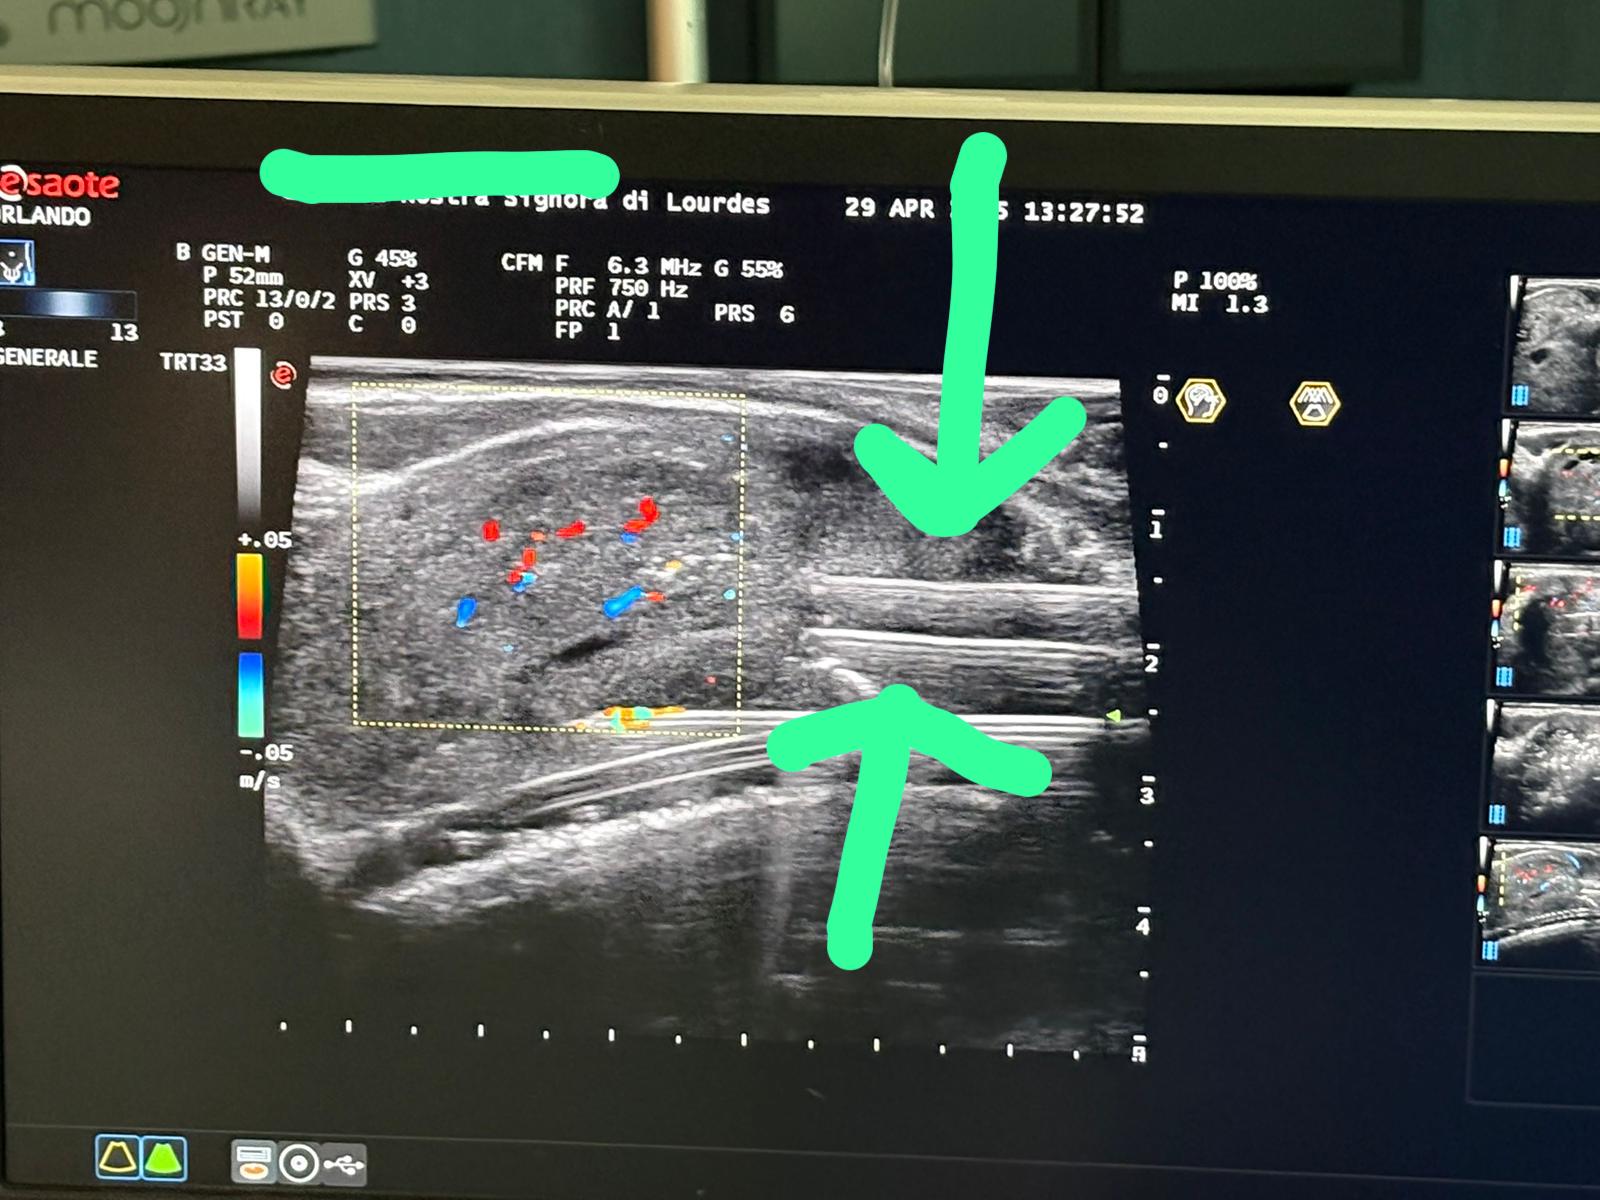

TPLA - Terapia Termica Laser Percutanea Ecoguidata

Innovativa tecnica percutanea sotto guida ecografica. Esegue una necrosi controllata della porzione centrale della prostata. Indicato per prostate anche voluminose. Non necessita di resezione né cateterismo prolungato.